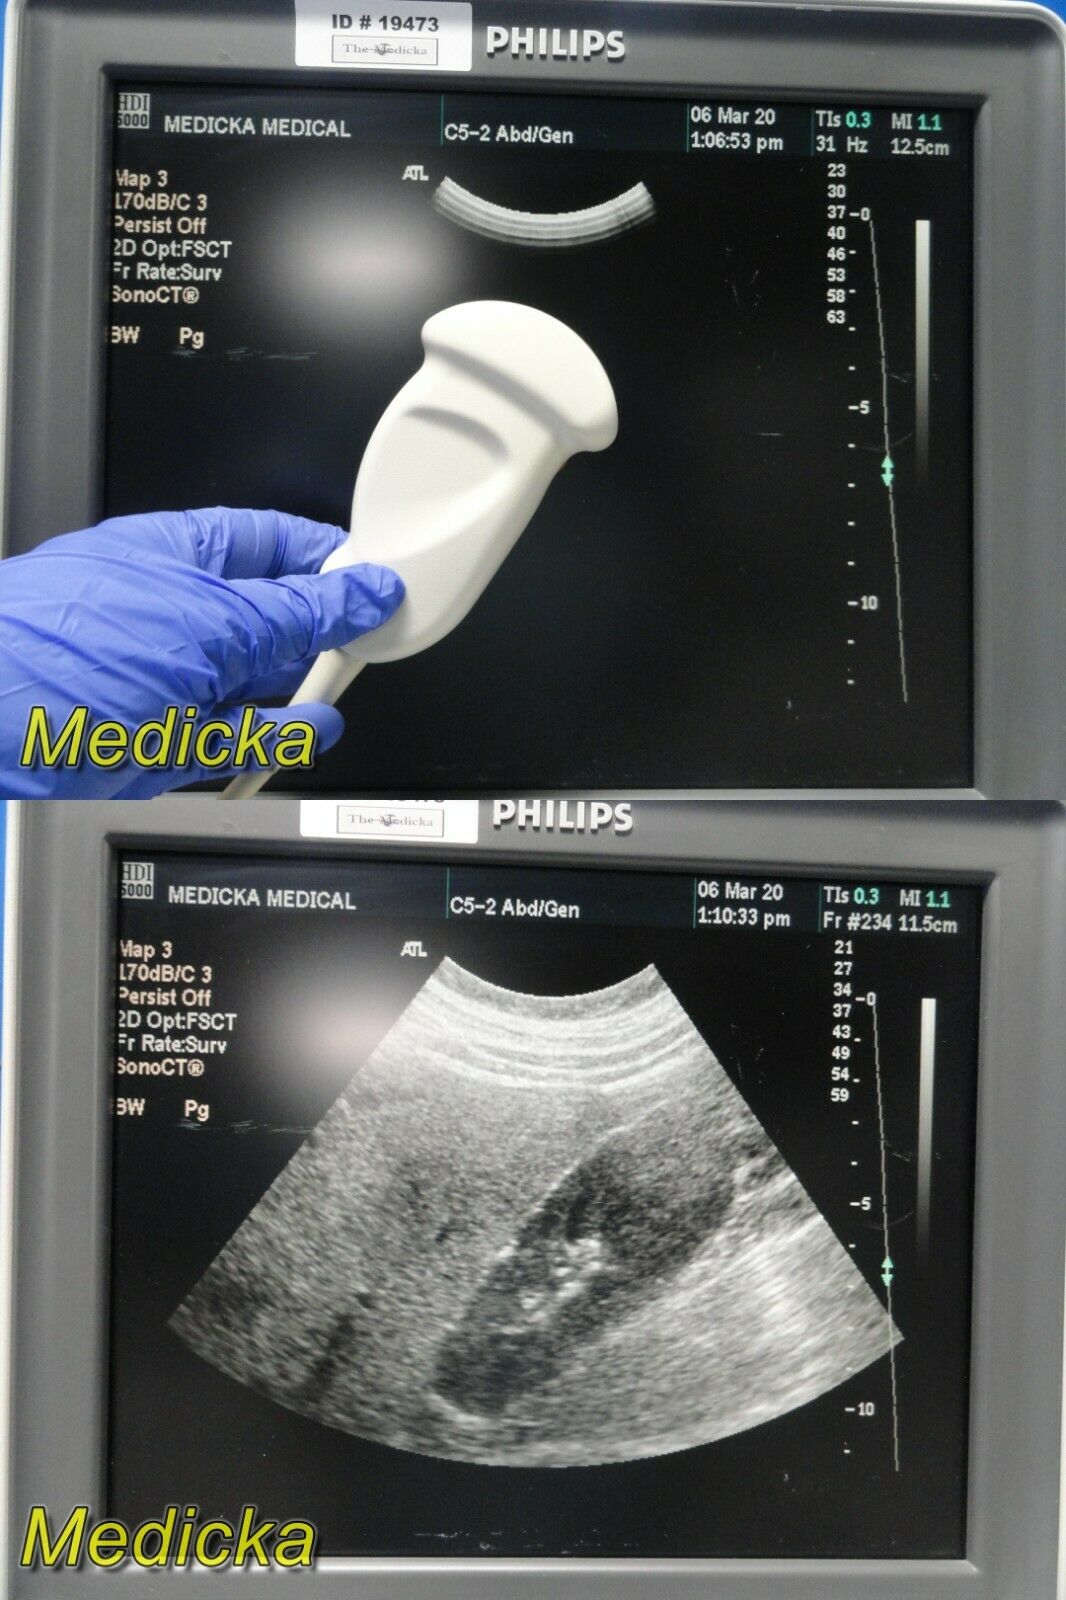

DIAGNOSTIC ULTRASOUND MACHINES FOR SALE

PHILIPS ULTRASOUND TRANSDUCER S4-1 PROBE

Sale price$ 1,228.36

DIAGNOSTIC ULTRASOUND MACHINES FOR SALE

PHILIPS S12-4 ULTRASOUND TRANSDUCER PROBE

Sale price$ 4,305.00